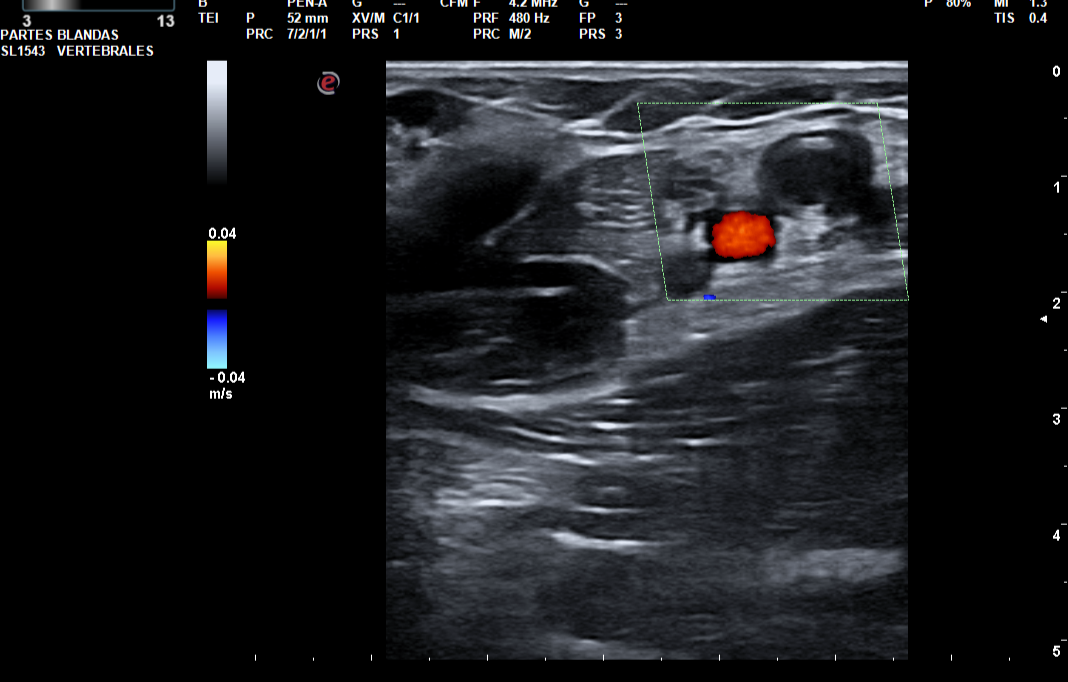

Hallazgos ecográficos

Trombo flotante en la confluencia yugulosubclavia. Ocupación por material hipoecogénico sugerente de trombosis venosa aguda, de la vena subclavia y ramas tributarias regionales, vena axilar, confluencia entre la vena cefálica (trombosada solo en su segmento más proximal a la confluencia) y axilar, así como de las venas braquiales hasta el codo.

La presencia de una trombosis venosa profunda en miembro superior, y la edad de la paciente hacen que se piensen en patologías autoinmunes, neoplásicas, como agentes causales de tal clínica.